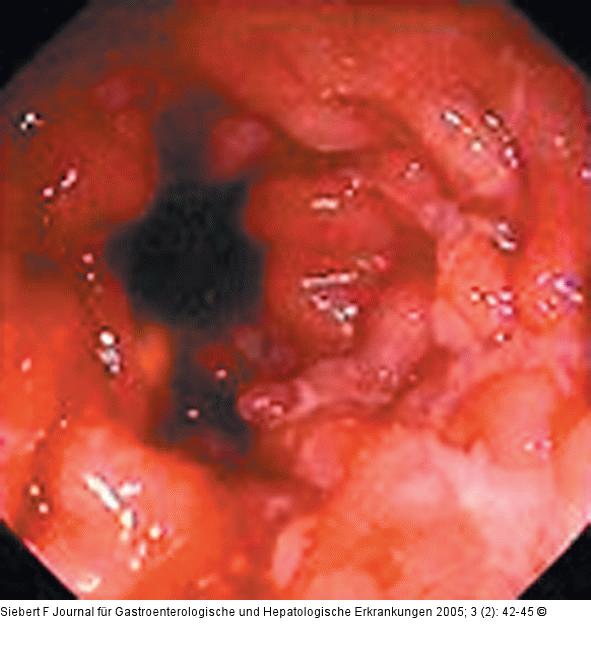

Abbildung 7a-c: Kolon-Ischämie - Differentialdiagnosen Differentialdiagnose Infektiöse Colitis - Strahlencolitis - Colitis ulcerosa (von oben nach unten) |

Abbildung 7a

Abbildung 7a-c: Kolon-Ischämie - Differentialdiagnosen

Differentialdiagnose Infektiöse Colitis - Strahlencolitis - Colitis ulcerosa (von oben nach unten) |